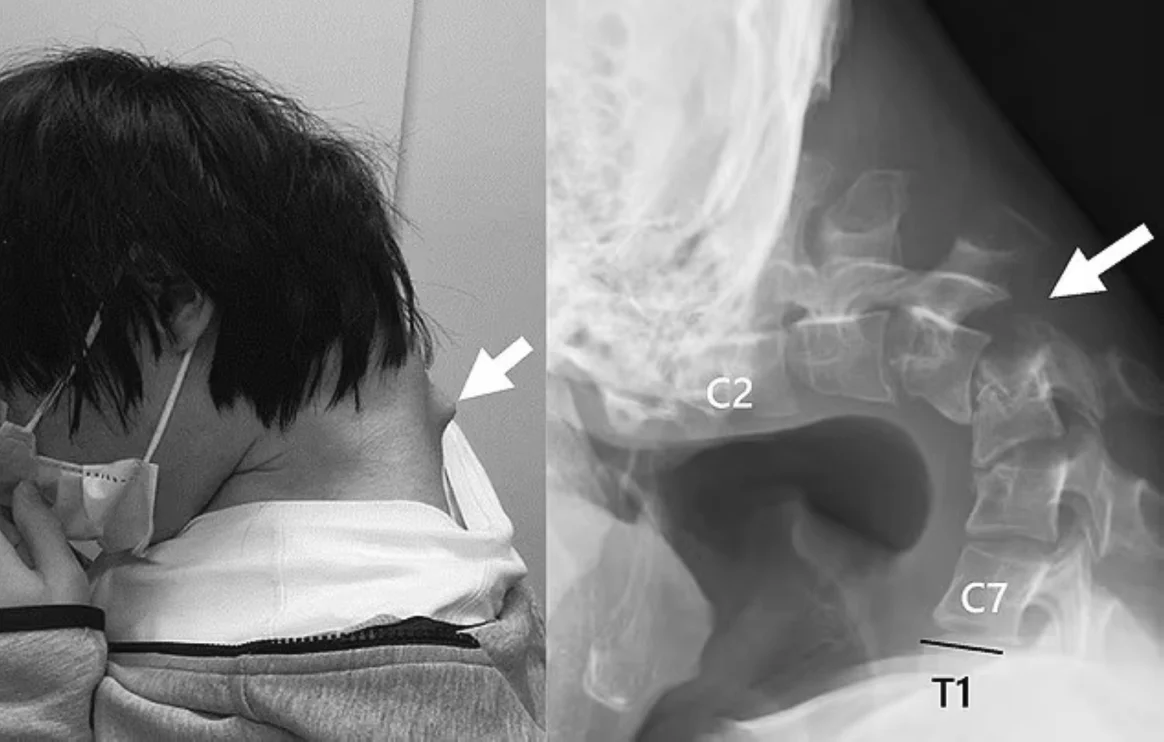

حذّر الباحثون بمركز “أويتا” الياباني لجراحات تقويم العظام، من مخاطر الوضعيات الخاطئة المرتبطة بالاستخدام المفرط للهواتف الذكية، بعد تسجيل حالة نادرة لشاب بريطاني أصيب بما يُعرف بـ”متلازمة الرأس المتدلي”.

وأفاد الباحثون في دراستهم المنشورة بدورية ” JOS Case Reports” الطبية، أن الشاب أمضى فترات طويلة منحنياً على هاتفه أثناء اللعب، ما أدى إلى تلف عضلي تدريجي تطلّب علاجًا فيزيائيًا مكثفًا، مؤكدين أن هذه الحالات بدأت تظهر بشكل متزايد بين الشباب والمراهقين.